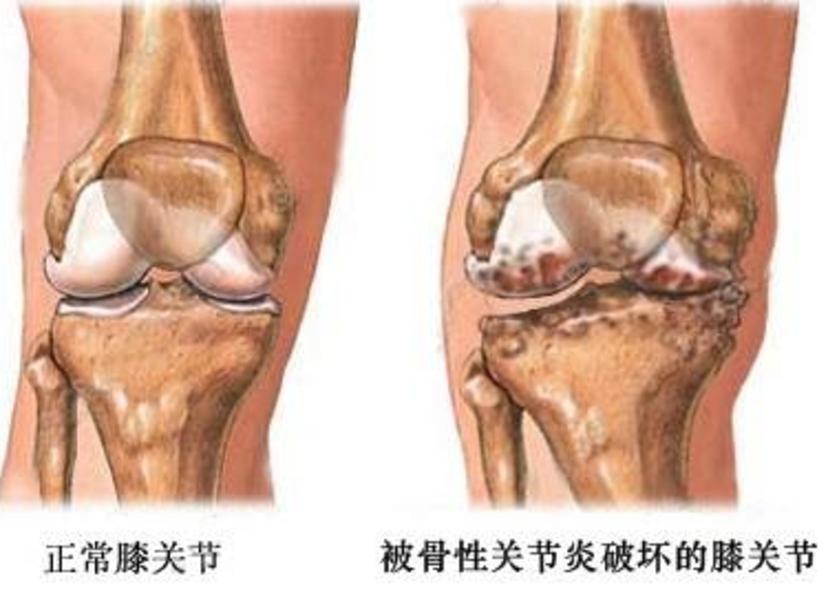

膝关节骨关节炎(Knee Osteoarthritis,KOA),是一种以膝关节软骨退行性改变和继发性骨质增生为特征的慢性关节疾病。膝关节炎症状缓慢进展,逐渐出现膝关节疼痛、肿胀、活动受限以及畸形等,严重影响日常行走。

随着病情的进展,膝关节开始出现内翻、外翻、旋转或者屈曲挛缩畸形,其中膝关节内翻是膝关节骨关节炎最常见的关节畸形。

除了典型的骨关节炎症状外,X片检查是诊断膝关节骨关节炎的金标准。X片可见关节间隙变窄,周边骨赘形成,软骨下硬化或囊性变。